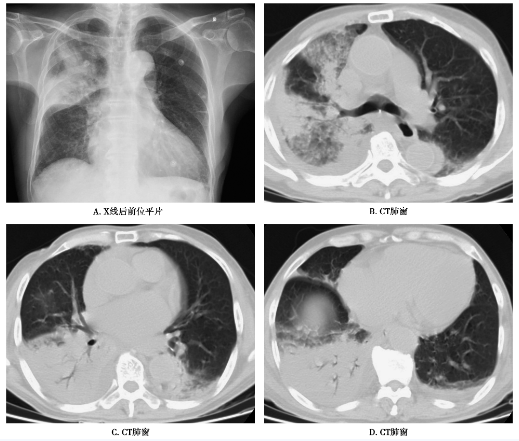

图2

图2A~D 右肺及左下肺细菌性肺炎。右肺及左下肺见散在大片实变影及少许磨玻璃影,边缘模糊,病灶以右肺分布明显,内可见空气支气管征。气管、双侧主支气管及其主要分支尚通畅。双侧胸腔少量积液